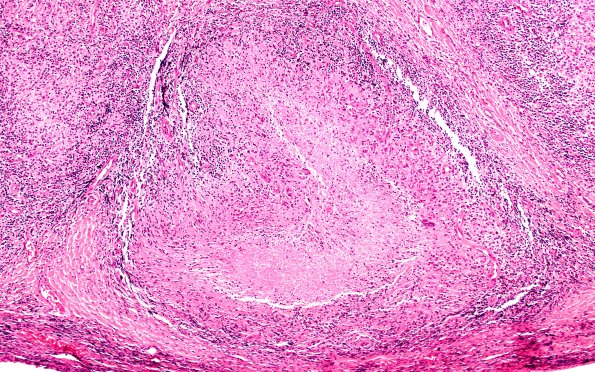

5B1 Leprosy, Tuberculoid (Case 5) 10X A

5B1-3 Not uncommonly, caseating necrosis is seen. (H&E)